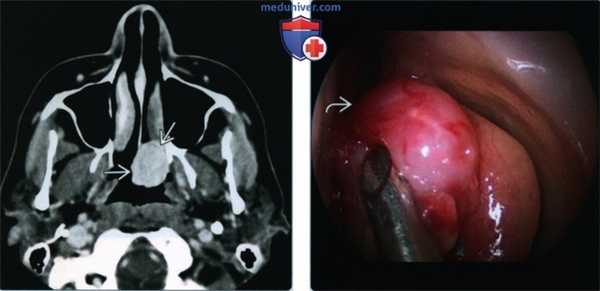

(Слева) При аксиальной МРТ STIR визуализируется инвертированная папиллома с типичной архитектурой, напоминающая кору мозга. «Запертый» секрет снаружи гипоинтенсивен по сравнению с папилломой. Папиллома редко возникает в лобной пазухе.

(Справа) При корональной МРТ Т1 С+ FS визуализируется инвертированная папиллома в решетчатых пазухах и в лобной пазухе. «Запертый» секрет вдоль края опухоли в лобной пазухе содержит белок (укорочение Т1).

3. МРТ при синоназальной инвертированной папилломе:

• Т1 ВИ:

о Изо- или слегка гиперинтенсивный сигнал по сравнению с мягкими тканями и мышцами

• Т2 ВИ:

о Неоднородный, преимущественно гиперинтенсивный сигнал по сравнению со скелетными мышцами

- Бороздки, напоминающие кору мозга,-отличительный признак

о Зоны некроза и «запертый» секрет: гиперинтенсивный сигнал на Т2

• Т1 ВИ С+:

о Контрастирование может иметь конволютивный, церебриформный характер

о Если часть опухоли выглядит инвазивной или обнаруживается некроз → синхронный ПКР